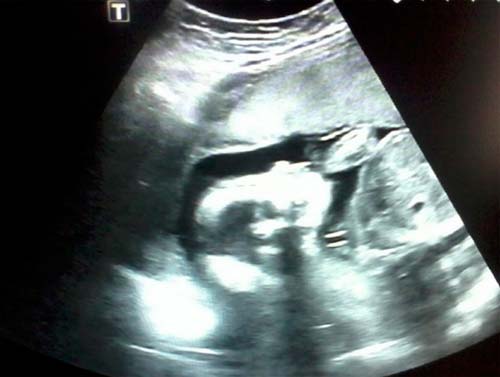

Foto de ultrassom com 21 semanas (clique para ampliar):

Com uma localização bem-sucedida do feto, você pode descobrir o sexo do bebê. Mas o futuro menino ou menina às vezes pode "esconder" até o nascimento.

Se você não fez um ultrassom no segundo trimestre, ele será indicado. Um médico especialista verificará as principais dimensões do corpo e membros do feto, a condição dos órgãos internos e vários outros indicadores. A placenta não será menos minuciosamente examinada.